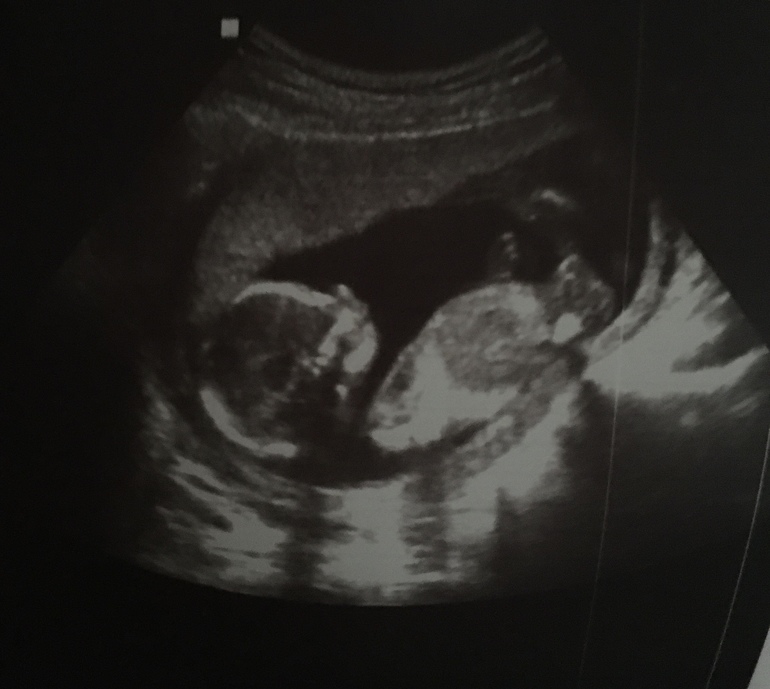

УЗИ, КТГ, доплерСегодня ходила на сроке 16,1 на узи, и там показали во всех подробностях мою девочку, так что крашу кружок в розовый 💕

Все параметры в норме, все хорошо, и даже шейка 37, надеюсь, так и будет дальше, но после 2 скрининга буду делать цервикометрию каждые пару недель.

Малышка махала рукой, такие чувства нахлынули нежные